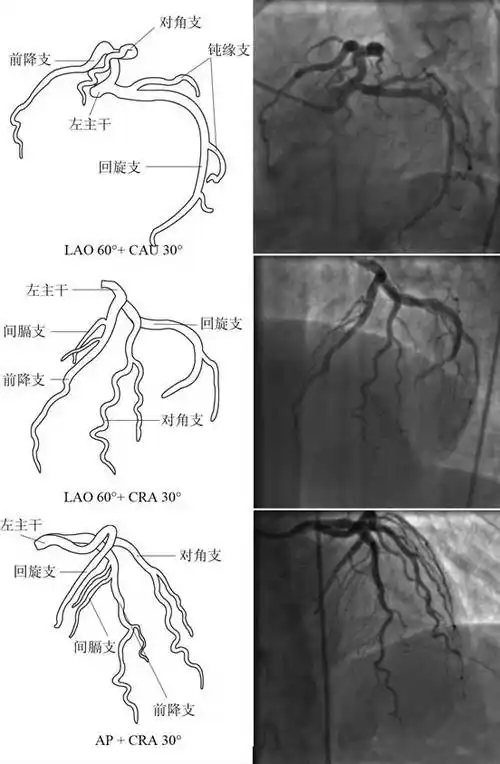

冠心病造影检查心肌梗塞,冠脉介入术是非常有效的重建冠状动脉灌注的